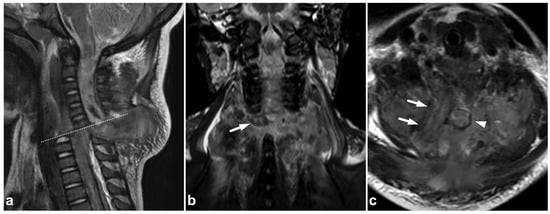

5.4. Vascular Injuries

CTA has been a workhorse in suspected vascular trauma for decades. On a routine cervical spine MRI, an arterial injury can be detected as an abnormal flow void in T1-weighted, T2-weighted, STIR, and proton density sequences (Figure 14). Vessel wall injury (dissection or intramural hematoma) can be seen in routine sequences. When in doubt, modern vessel wall imaging techniques with a high spatial and contrast resolution can significantly improve the detection and characterization of even minor arterial injuries [57,58,59].

Figure 14.

(a) Axial T2-weighted. (b) Axial plane of an isotropic fat-saturated T1-weighted (black blood sequence). (c) Right-sided off-midline sagittal STIR. (d) Left-sided off-midline sagittal STIR. (e) Axial trace diffusion-weighted image of the brain. (f) Axial apparent diffusion coefficient map of the brain. A 5-year-old male, found with impaired consciousness in unclear circumstances. MRI was performed to exclude trauma and revealed an occluding dissection of the right vertebral artery. The occluded right vertebral artery lacked a normal flow void on T2-weighted and STIR images (white arrows), while the patent left vertebral artery presents a normal flow void (white arrowhead). T1 fat-saturated sequence (b) reveals an intramural hematoma with a bright T1 signal in the wall of the dissected artery caudally to the completely occluded segment (curved arrow). Diffusion-weighted brain imaging demonstrates right-sided pontine infarction as a sequel to vertebral artery occlusion (black arrowheads). No other findings were suggestive of acute injury in the cervical spine or in the brain. The cause of the dissection remains unknown.